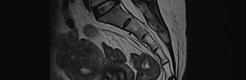

- ¾î±ú Áúȯ ±ÞÁõ'¾î±ú°¡ ¹«°Å¿î »ç¶÷'µéÀÌ ¸¹Àº Å¿Àϱî. ¾Æ´Ï¸é ½ºÅ°, °ñÇÁ, ¼ö¿µ, ¹èµå¹ÎÅÏ µî ¿îµ¿ÇÏ´Â »ç¶÷µéÀÌ ±ÞÁõÇϰí Àֱ⠶§¹®Àϱî. ¾î±ú ¾ÆÇ »ç¶÷ÀÌ Å©°Ô ´Ã°í ÀÖ´Ù.°Ç°º¸..